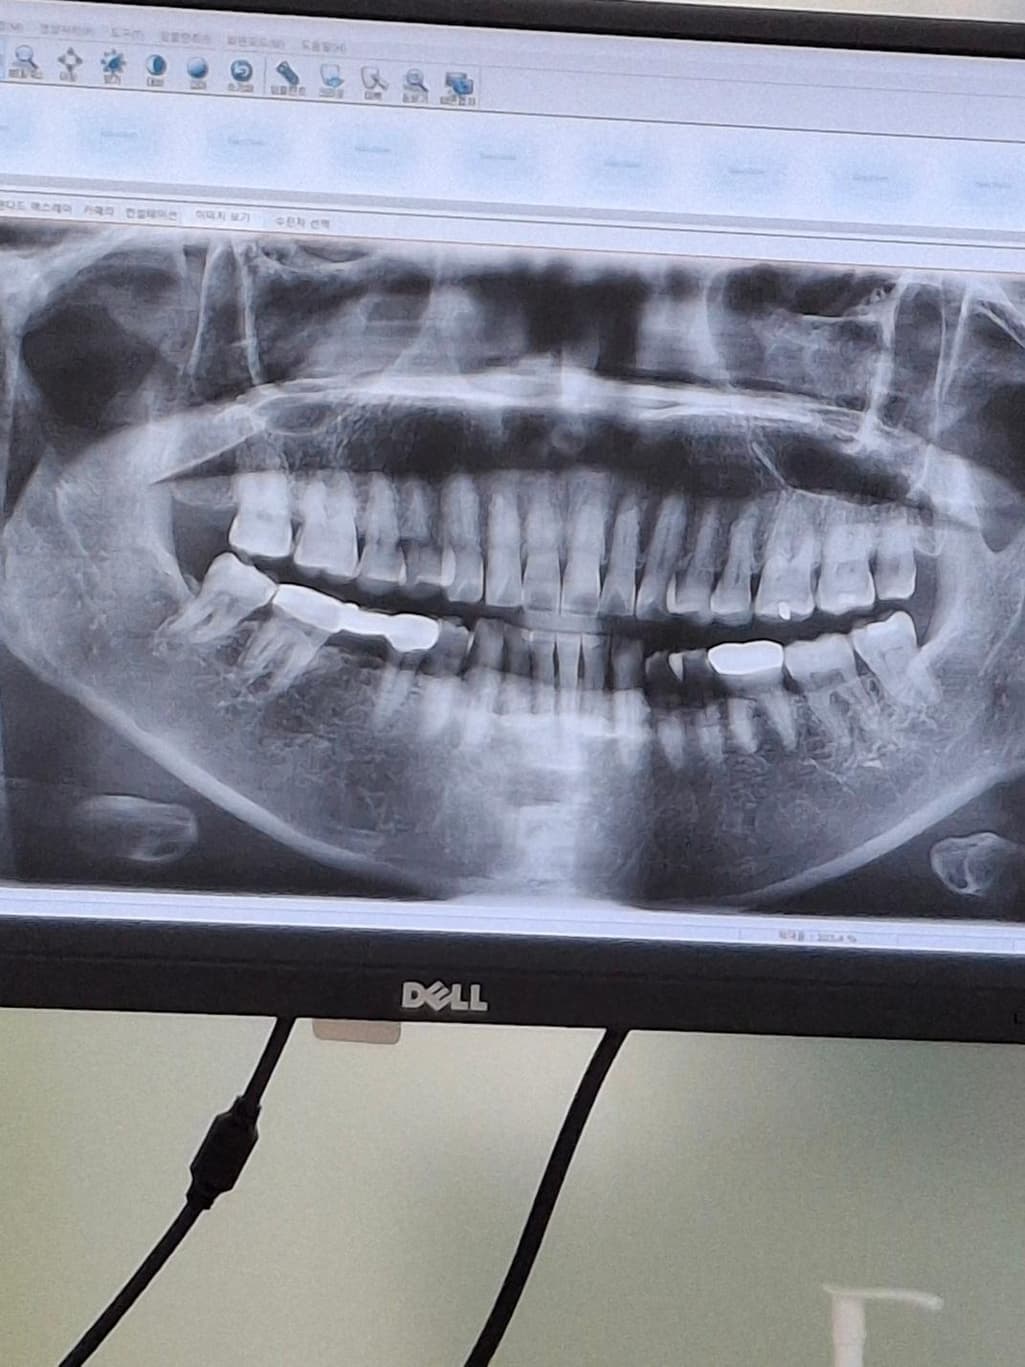

• 2번 째 사진

파노라마 사진을 봤을 경우에 치근단 질환이 있는 치아는 보이지 않습니다. 설측의 외골증이 있는 부분에는 잇몸이 얇게 있기 때문에 너무 딱딱한 음식을 먹거나 하면 잇몸에 상처가 생길수 있습니다.

음식을 먹을때 천천히 먹는다면 잇몸에 상처가 나는 빈도를 줄일수 있습니다